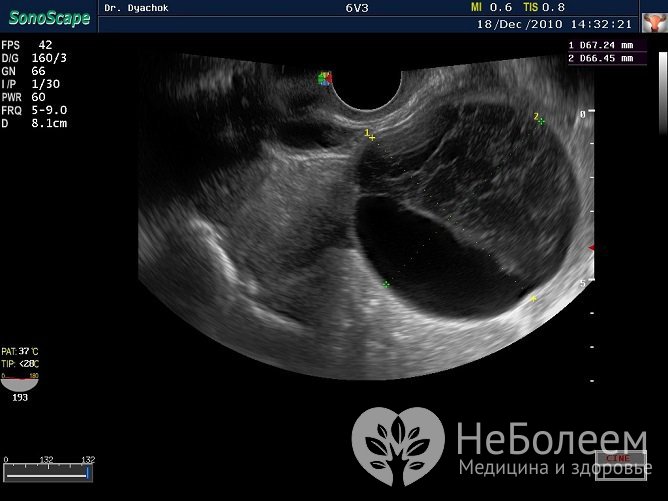

К основным методам диагностики патологии относится, в первую очередь, ультразвуковое исследование органов малого таза. Также могут проводиться гинекологический осмотр, лабораторные анализы, компьютерная и/или магниторезонансная томография, диагностическая лапароскопия.

Киста желтого тела диагностируется по результатам УЗИПри небольшом размере лютеиновой кисты и отсутствии каких-либо симптомов выбирается выжидательная тактика, так как новообразования данного вида часто рассасываются самостоятельно. У беременных лютеиновая киста обычно исчезает ко II триместру.